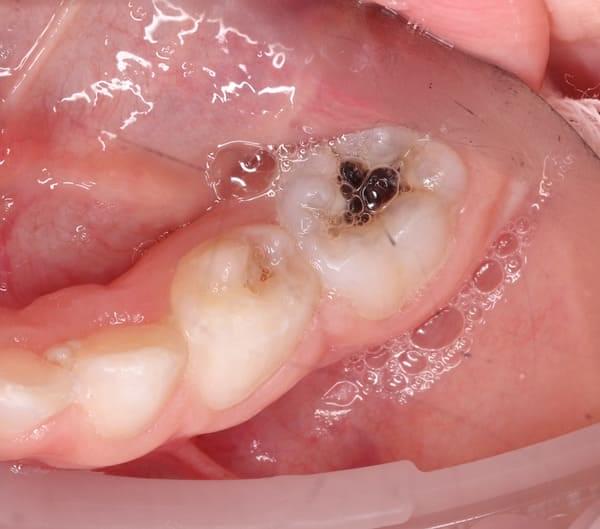

Поява перших постійних зубів, а це шості зуби, відбуваються, коли дитина ще не може, як слід провести їх гігієну та попіклуватись про їх здоров’я. Тому, на жаль вони і вражаються карієсом досить швидко. Пацієнт ще маленький – 6 років, а лікування потребує дорослого: зі знеболенням та ізоляцією. Саме таке і було проведене в даному випадку: зуб очищений від інфікованих тканин, відновлений фотополімерним матеріалом і готовий довго служити юному господарю.